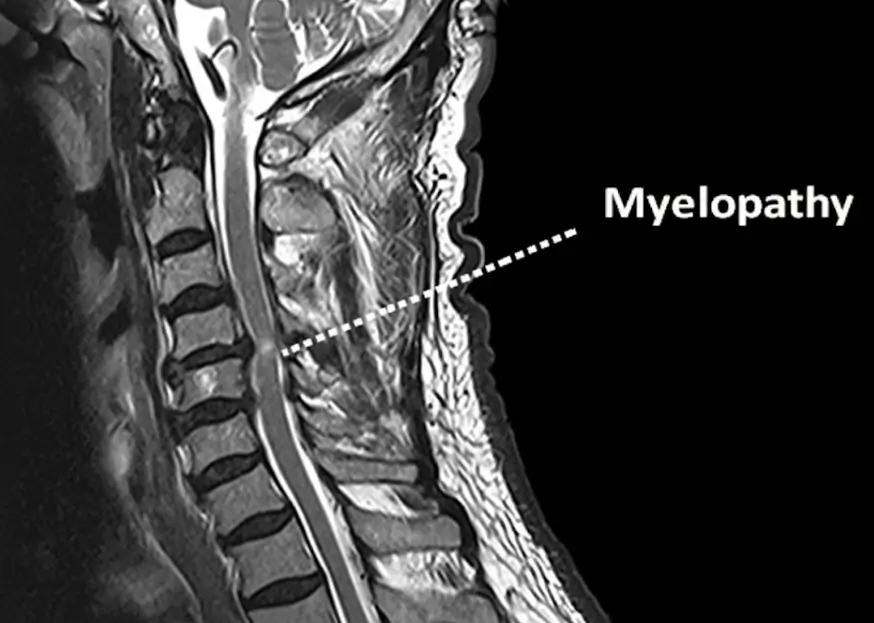

What Is Spinal Myelopathy?

Spinal myelopathy occurs when the spinal cord becomes compressed, usually because of changes in the bones, discs, or ligaments surrounding it. This compression disrupts the signals that travel between your brain and the rest of your body, leading to weakness, coordination issues, and even numbness.

Because spinal myelopathy affects the spinal cord directly, accurate diagnosis is essential. Dr. Wong uses advanced imaging and neurological testing to pinpoint the exact cause and severity of compression. These may include:

- MRI scans, to view soft tissues, discs, and the spinal cord